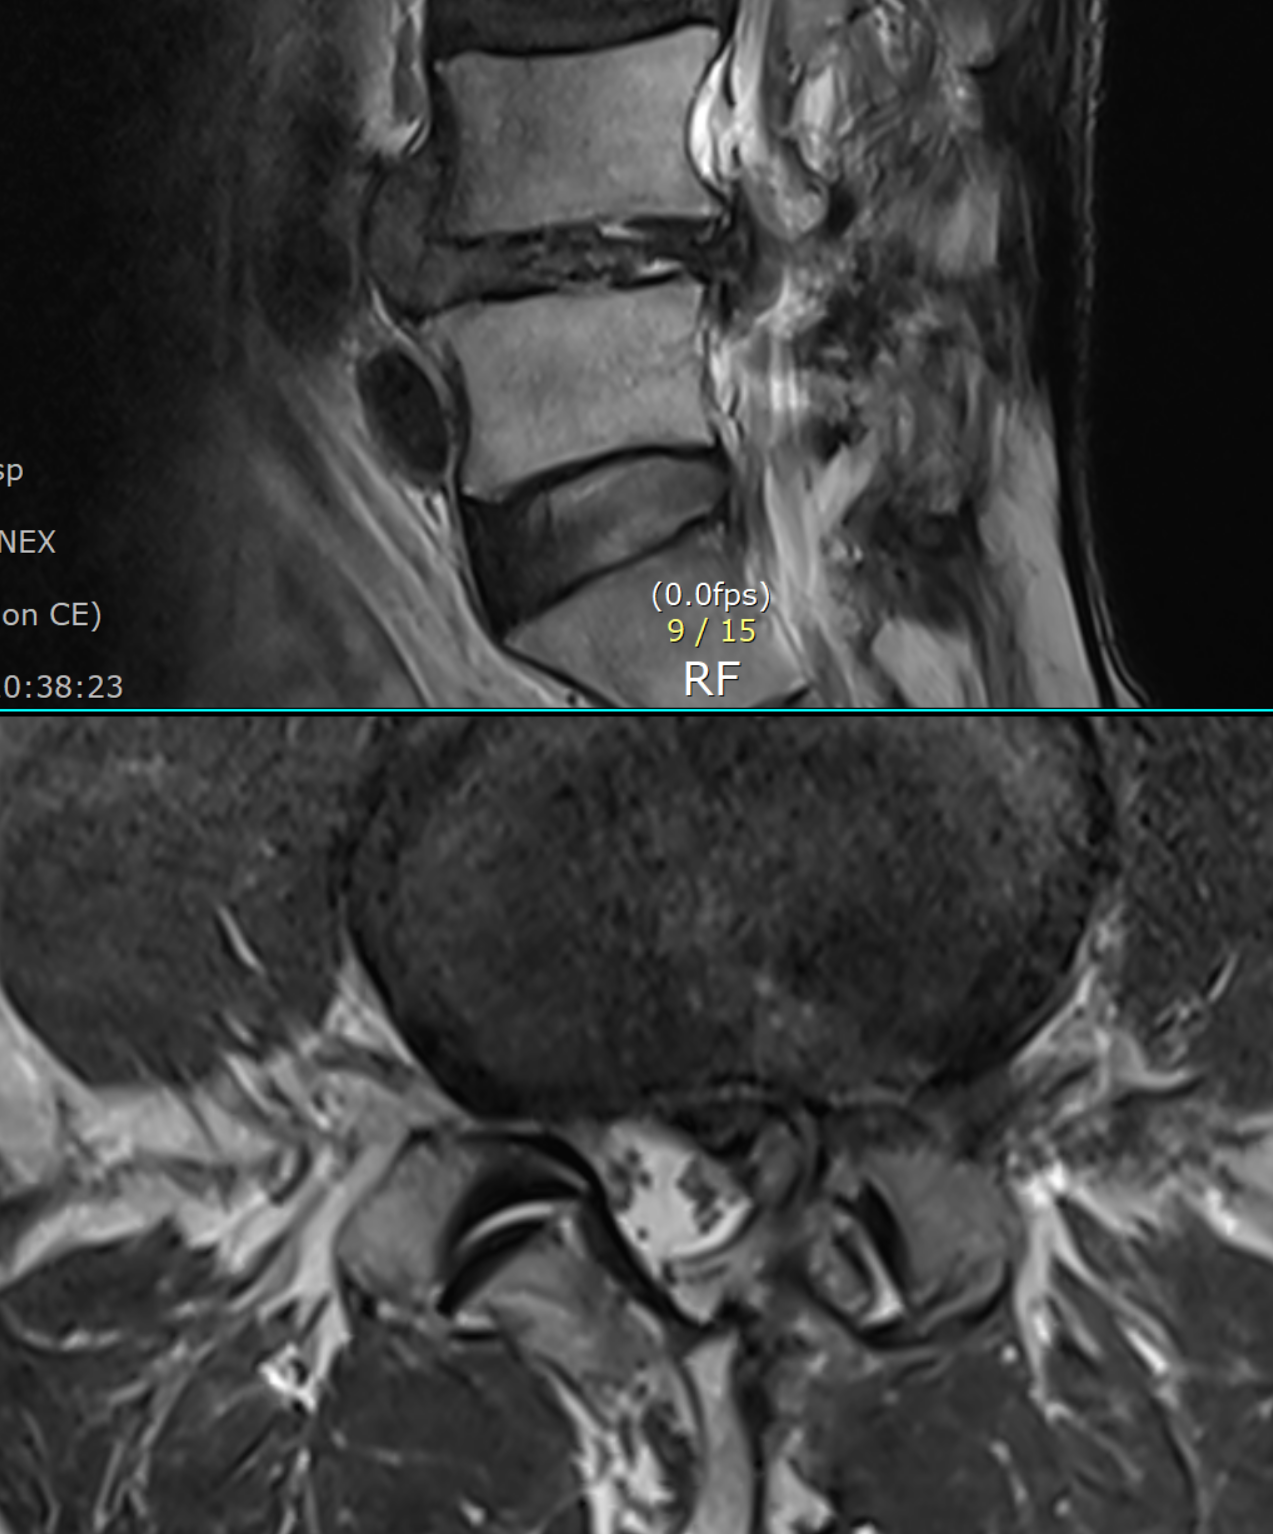

- 배경: adhesion at L5 root

- mri 상 25년에 비해 granulation 은 감소, extrusion -> small protrusion 으로 변화